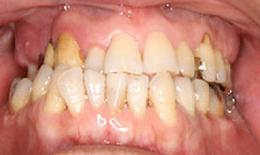

治療後

上顎

保存困難な歯を抜歯後、インプラントを2本埋め込んで、セラミックスクラウンを被せた

下顎

インプラントを2本埋め込んで、セラミックスクラウンを被せた